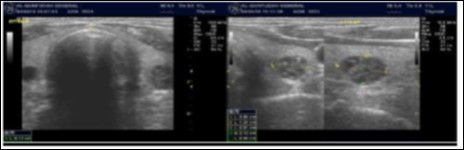

The reported prevalence of nodular thyroid disease depends on the population studied and the methods used to detect nodules 16. Our study population is unique as it is composed entirely of ESKD patients. We also used ultrasound as a method of detecting thyroid abnormalities. In our study the prevalence of thyroid nodular pathology as detected by ultrasound was found to be 57.6% mirror image what reported in the literature as it has been reported that nodules found on ultrasonography suggest a prevalence of 19 to 67%17, 18; and in other publications it has been reported to range from 50% to 70% 7, 8. Figure 3A below shows an Ultrasound detected thyroid nodule.

High-resolution ultrasonography (USG) is the most accurate and cost-effective method for evaluating and observing thyroid nodules 3. Although there is some overlap between ultrasound appearance of benign and malignant nodules, certain USG features are helpful in differentiating the two. Iso-or hyper-echogenicity of the thyroid nodule in conjunction with a spongiform appearance is the most reliable criterion for benignity of the nodule on gray-scale ultrasound, Figure 4A. Other features like nodule size <1 cm, width > length, presence of hypoechoic or hyperoechoic halo around the nodule, Figure 4A and Figure 4B, caused by fibrous capsule compressing thyroid tissue, and coarse/curvilinear calcification are less specific but may be useful ancillary signs4 ,6. "Ring down" or "comet-tail" artifact or sign is typical of benign cystic colloid nodule, Figure 520. Perinodular flow or spoke-and-wheel-like appearance of vessels on color Doppler examination is characteristic of a benign thyroid nodule. However, this flow pattern may also be seen in thyroid malignancy. A complete avascular nodule is very unlikely to be malignant 4.

Figure 4B.Isoechoic nodule with Hyperechoic rim

In our study many patients were found to have nodules look very much like PT adenoma, Figure 7 below. At least, 4 patients were subsequently confirmed to have parathyroid adenomas, Figure 8 and 2 patients underwent surgery

Despite the fact that nodular pathology was found to be very prevalent among our study population, it has been found difficult to differentiate between thyroid and parathyroid pathology using ultrasound alone. However, some characteristics of the parathyroid glands might suggest parathyroid pathology in the context of the clinical picture of secondary or tertiary hyperparathyroidism which is very prevalent in ESKD patients’ populations.

Figure 7.Thyroid nodule suspicious for Parathyroid adenoma due to its location

Figure 8.Nodule that proven to be a parathyroid adenoma, volume =5265 mm3